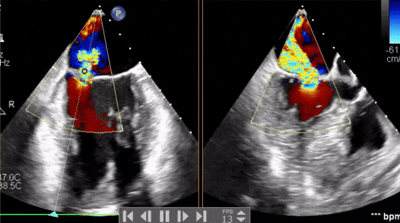

術(shù)前術(shù)后對(duì)比

術(shù)前

術(shù)后

術(shù)后超聲

反流變?yōu)檩p度,反流等級(jí)從4+降為1+;

術(shù)后平均跨瓣壓差1mmHg;

夾子夾合量:前葉15mm,后葉10mm;

剩余瓣環(huán)面積:術(shù)后有效瓣環(huán)面積3.7cm²;

二尖瓣3區(qū)可見(jiàn)夾子強(qiáng)回聲,位置固定。